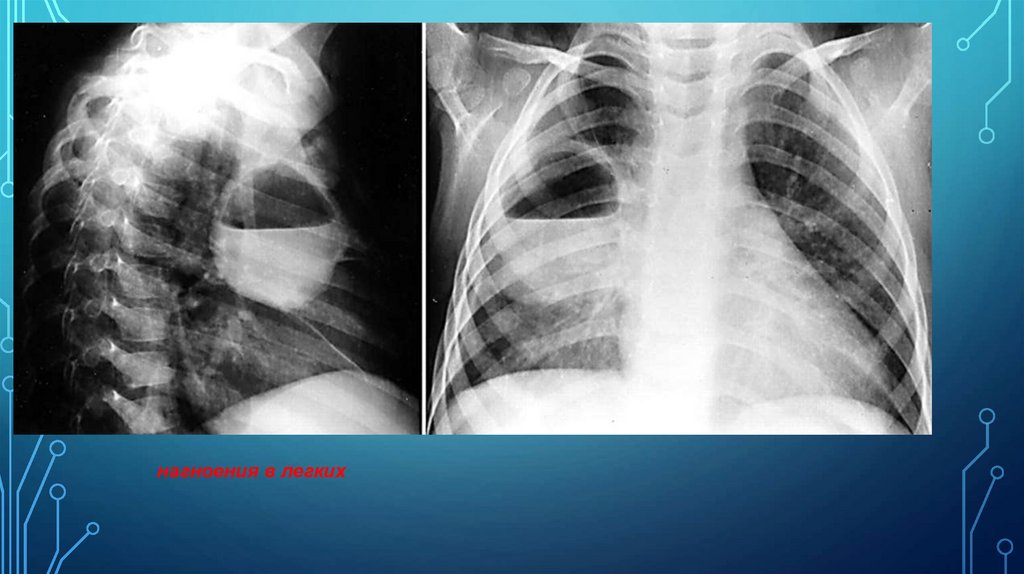

нагноения в легких

116. Рис. 17а. Диагноз: Абсцедирующая пневмония правого легкого.

РИС. 17А. ДИАГНОЗ: АБСЦЕДИРУЮЩАЯ ПНЕВМОНИЯ ПРАВОГО

ЛЕГКОГО.

Н.С. ВОРОТЫНЦЕВА, С.С. ГОЛЬЕВ РЕНТГЕНОПУЛЬМОНОЛОГИЯ